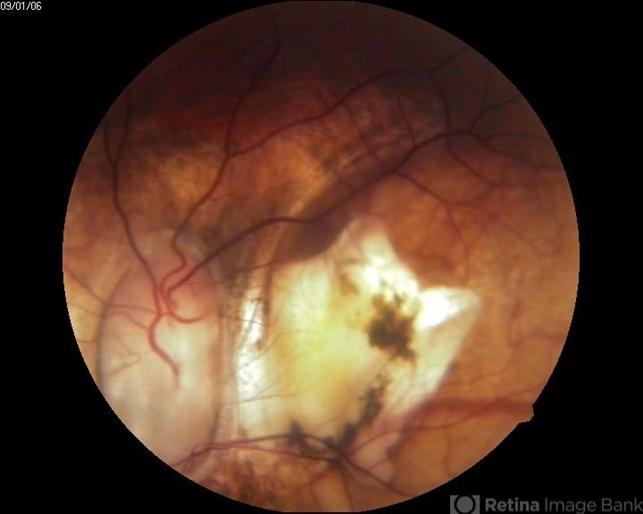

- posterior staphyloma

- A 40-year-old male presented with complaint of gradual diminished vision.